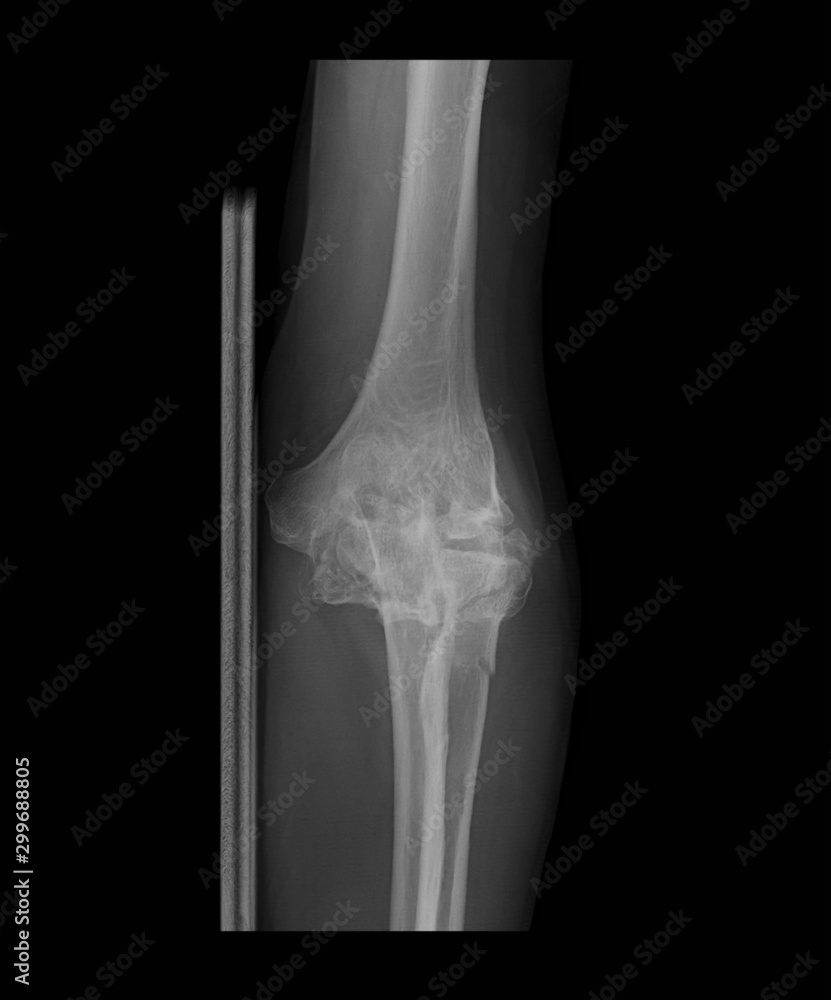

Left Elbow X Ray Image - Frontal radiograph of the elbow with labels. The image displays the inner structure (anatomy) of. Web the elbow series is a set of radiographs taken to investigate elbow joint pathology, often in the context of trauma. Soft tissue areas, cortical margins, trabecular patterns, bony alignment, joint. Web anteroposterior (ap) and lateral radiographs remain the workhorses of elbow imaging.

Left Elbow X Ray Image - Soft tissue areas, cortical margins, trabecular patterns, bony alignment, joint. Web the elbow series is a set of radiographs taken to investigate elbow joint pathology, often in the context of trauma. Web anteroposterior (ap) and lateral radiographs remain the workhorses of elbow imaging. Web a recommended systematic checklist for reviewing musculoskeletal exams is: Oblique radiograph of the elbow with labels.